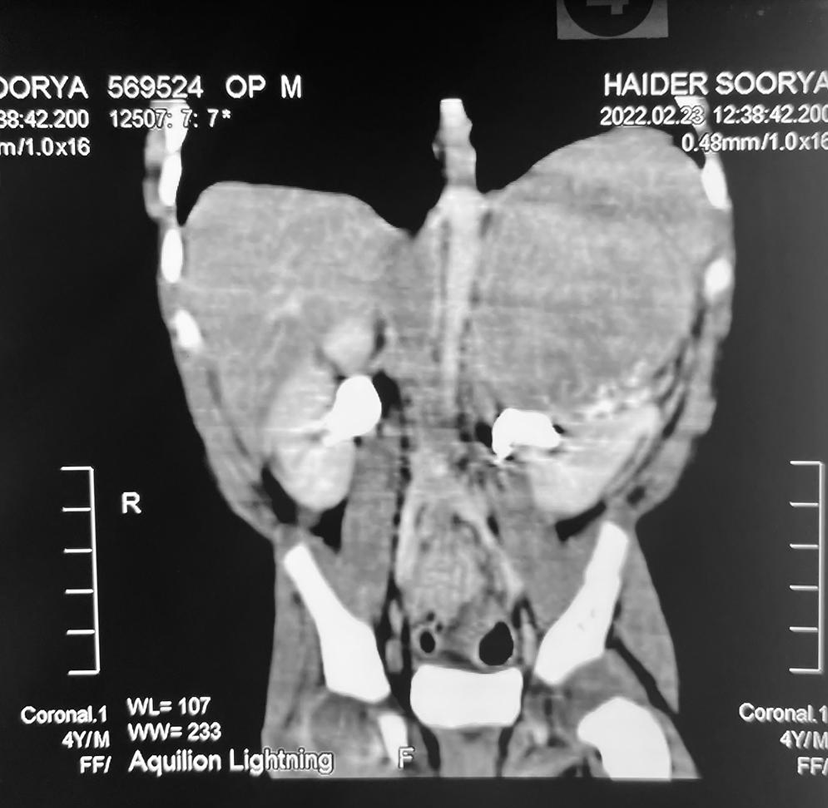

An abnormal growth in the belly is known as an abdominal mass. It results in obvious swelling and could alter how the abdomen looks. You can have symptoms like weight gain and bloating, soreness, and discomfort in your abdomen.

The location of abdominal masses is frequently used to describe them. There are four quadrants, or divisions, of the abdomen. The right upper quadrant, left upper quadrant, right lower quadrant, or left lower quadrant are all possible locations for an abdominal mass. The epigastric part and the periumbilical region are the other two divisions of the stomach. The epigastric region is situated above the belly button and below the ribs, whereas the periumbilical section is situated below and surrounding the belly button. Many abdominal masses can be treated. Nevertheless, the cause of the mass may have an impact on potential health issues.

Abdominal masses can be the result of a number of factors, including an injury, cyst, benign tumor, cancer, or other disease.